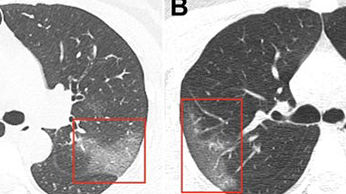

Hình ảnh phổi bệnh nhân nhiễm Covid-19 bị virus Corona tàn phá

Y học thường thức -  06/03/2020

Đây là hình ảnh chụp CT phổi của một phụ nữ 33 tuổi ở bệnh viện Lan Châu, Trung Quốc. Cô nhập viện trong tình trạng sốt và ho trong 5 ngày, bác...